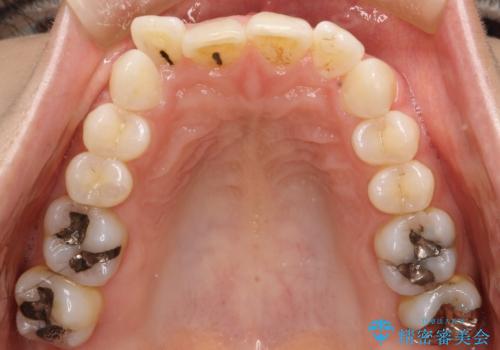

- 前歯のがたつきを気にされて来院されました。

右上の前から2番目の歯が前方に大きく傾いており、下の前歯もガタガタしていました。

インビザラインにて、歯と歯のあいだをわずかに削り並べる計画としました。